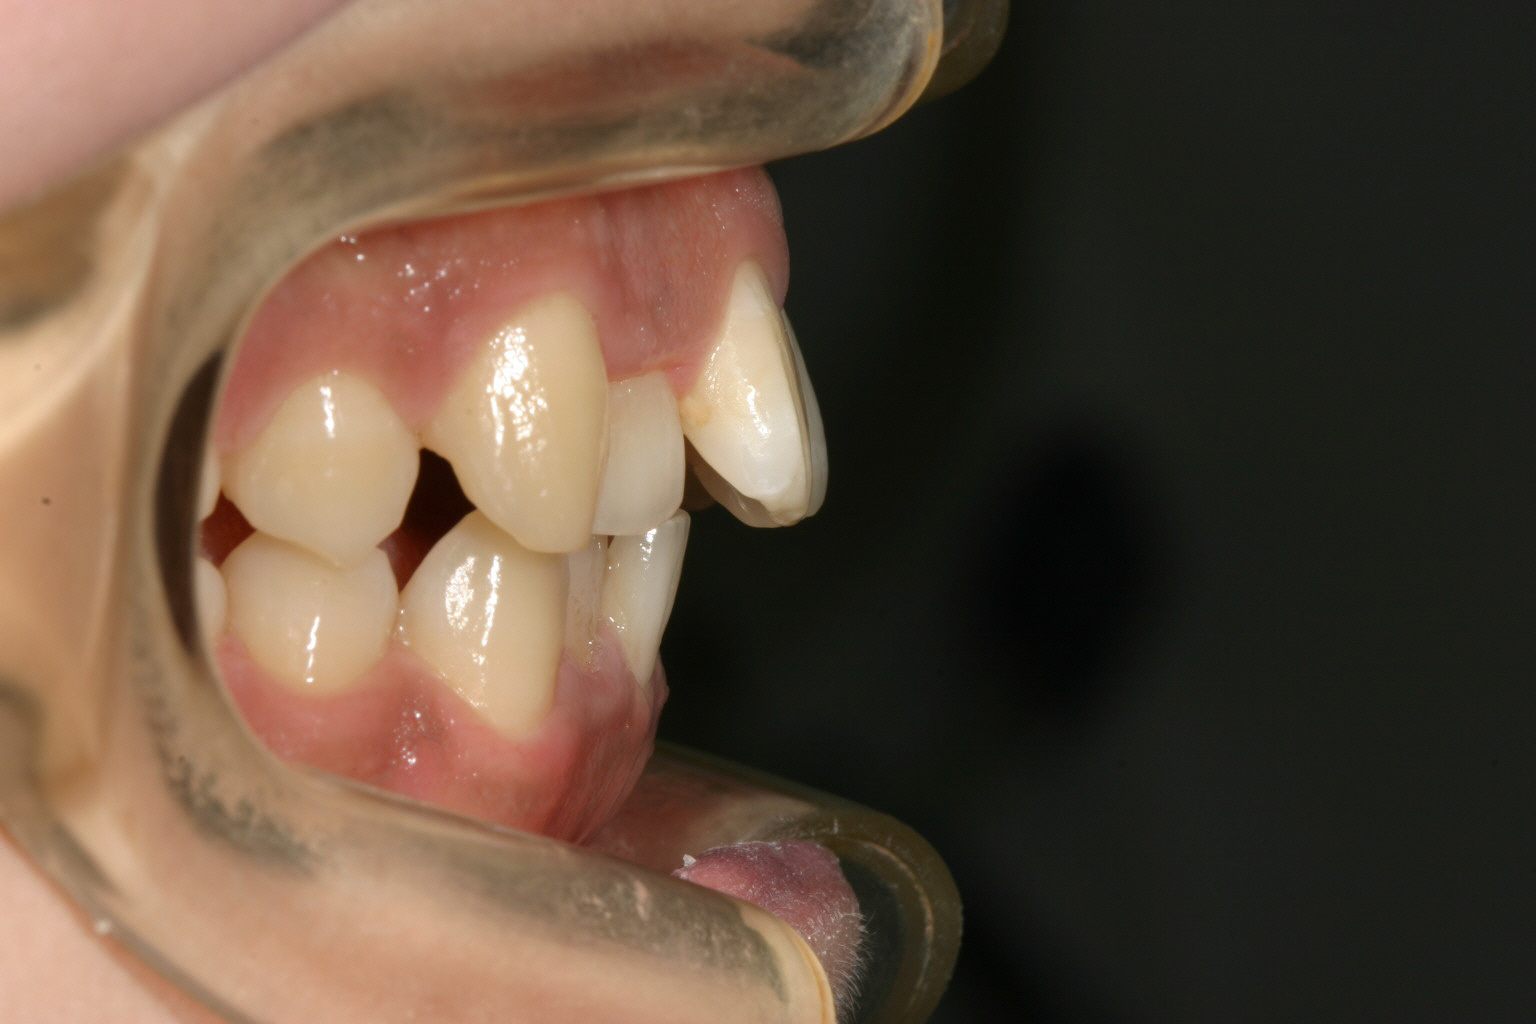

前歯が飛び出して少し翼状捻転しています。

下顎は少しの叢生です。

少しオーバージェットが大きいですね~